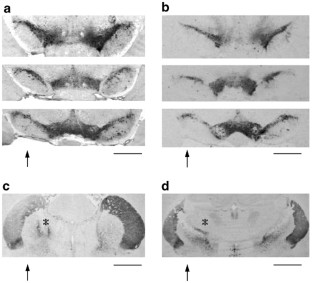

A new adenoviral vector (Ad-GFAP-GDNF) (Ad=adenovirus, GFAP=glial fibrillary acidic protein, GDNF=glial cell line-derived neurotrophic factor) was constructed in which (i) the E1,E3/E4 regions of Ad5 were deleted and (ii) the GDNF transgene is driven by the GFAP promoter. We verified, in vitro, that the recombinant GDNF was expressed in primary cultures of astrocytes. In vivo, the Ad-GFAP-GDNF was injected into the striatum of rats 1 week before provoking striatal 6-OHDA lesion. After 1 month, the striatal GDNF levels were 37 pg/μg total protein. This quantity was at least 120-fold higher than in nontransduced striatum or after injection of the empty adenoviral vector. At 3 months after viral injection, GDNF expression decreased, whereas the viral DNA remained unchanged. Furthermore, around 70% of the dopaminergic (DA) neurons were protected from degeneration up to 3 months as compared to about 45% in the control groups. In addition, the amphetamine-induced rotational behavior was decreased. The results obtained in this study on DA neuron protection and rotational behavior are similar to those previously reported using vectors with viral promoters. In addition to these results, we established that a high level of GDNF was present in the striatum and that the period of GDNF expression was prolonged after injection of our adenoviral vector.